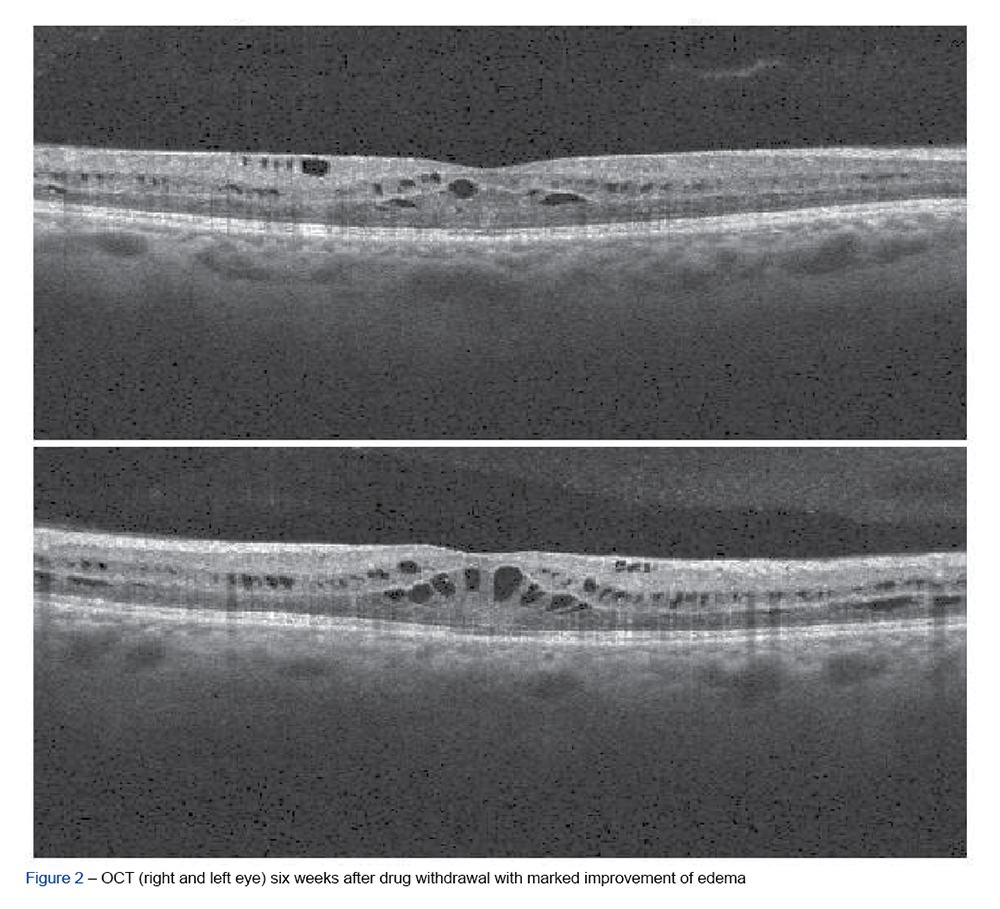

A 61-year old male was referred to the Ophthalmology department because of decreased bilateral visual acuity. The patient had metastatic pancreatic adenocarcinoma and ...